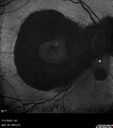

BRAO - plaques in vessels - GIF video of FA3 views78 year old female with vision loss for 1 week and old macular scar. Images show BRAO with plaques and FA shows occlusion.Oct 13, 2025